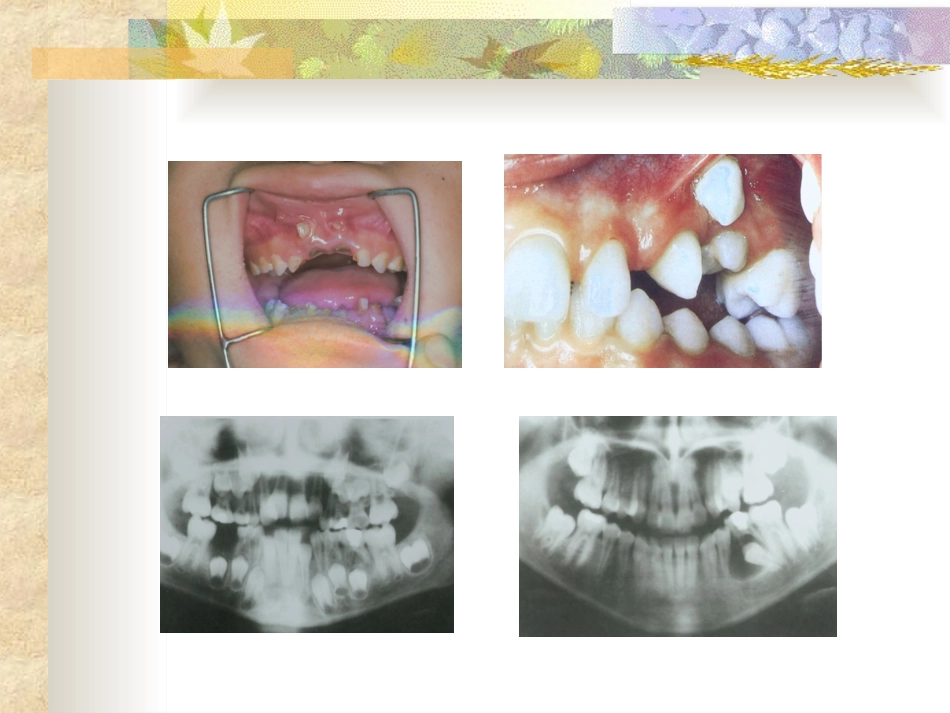

乳牙根管治疗一、乳牙的重要作用1.有利于儿童的生长发育。2.有利于恒牙的萌出及恒牙列的形成。3.有利于发音及保护心理。4.对全身的影响。二、乳牙根管治疗解剖生理特点1.有利点:a.根管粗大;b.根尖组织修复能力强。2.不利点:a.乳牙根生理性吸收—乳牙牙根稳定期;b.小儿配合差。三、乳牙根管治疗的适应症1.乳前牙外伤露髓,牙根发育完成者;2.牙髓坏死、根尖周炎应保留的乳牙。四、治疗步骤1.常规制洞。2.根管预备:a.活髓:局麻下拔髓或失活后拔髓;b.死髓:去除髓室和根管的坏死牙髓。使用根管器械扩挫根管。3.根管消毒。4.根管充填。五、注意事项:方法和步骤基本同恒牙,但治疗时应注意:1.术前拍X片,了解尖周病变和牙根吸收情况。牙根吸收已达1/3以上者,难获良好的疗效。2.预备根管时应测根管长度以防器械超出根尖孔,以免将感染物质推出根尖孔或损伤恒牙胚。3.不送牙胶尖。4.根充剂仅可采用可吸收的糊剂充填,不影响恒牙交替。5.术后应拍X片观察根充情况,分类:a.适充填:恰填或距根<1mm;b.欠充填:糊剂未充满根管,距根尖孔>1mm;c.超充填:糊剂超出根尖孔。大多数学者认为,适充填和超填成功率高,远期疗效好。六.现行常用的乳牙根管充填材料1.良好的乳牙根充剂应具备:a.杀菌性强;b.可以随乳牙根生理性吸收而吸收;c.凝固后不发生体积变化;d.能阻射X线;e.超填后对恒牙胚无害;f.容易充入或取出等优点。2.常用乳牙根充糊剂a.碘仿糊剂(丁氧膏+黄碘)组成:丁香油、氧化锌、碘仿缺点:使牙变色,个别发生吸收困难b.vitapex组成:氢氧化钙+碘仿+其他缺点:价钱昂贵c.FR糊剂成分:粉:氢氧化钙、氧化锌、硫酸钡等。液:愈创木酚、丙二醇、无水酒精。缺点:糊剂较粘稠,导入根管后不久即硬化,要求操作要熟练,也会使牙变色。d.黄连氧化锌糊剂组成:黄连提取液+氧化锌。七、疗效判定标准1.成功标准:a.术后及复查时无自觉症状;b.临床无阳性体征,患牙无异常松动,牙龈无红肿、瘘管,牙根正常无叩痛。c.X线显示病变消失或原有阴影缩小,超出糊剂已完全吸收,恒牙胚无异常发育。2.失败标准:a.患牙根充后及复查时临床出现不适主诉或阳性体征之一者,如自发痛,咬合痛,牙龈红肿,压痛和瘘管形成,牙齿异常松动,叩痛。b.X线显示:牙根病理性吸收或病变扩大等。八、乳牙保健宣传1.乳牙要定期检查,早发现、早就诊2.乳牙的治疗效果直接关系到恒牙的替换3.乳牙治疗过,不代表以后不会再出问题4.维护好孩子日常的口腔卫生,每日早晚刷牙谢谢!